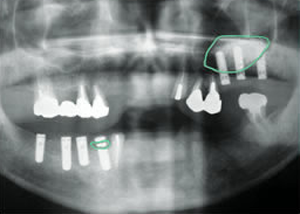

症例4 57歳女性

2009 6/21 更新

治療前

(下11本、上1本抜歯済み)

平成19年6月29日

1.下11本、上1本抜歯、同時に総義歯セット

2.総義歯セット 正面口腔内

3.総義歯の入った正面観

4.抜歯後1ヶ月 術面口腔内

5.抜歯後1ヶ月

上顎前歯部5本 インプラント埋入

6.前歯部インプラント

埋入より1ヶ月

左右臼歯部8本

インプラント埋入

7.下の前歯部に4本

8.この部は薄い骨があっただけでインプラントの先端1/3を骨に埋入。あとはすべて骨を作ってあります。

上にのせた膜の中にチタンのフレームがわずかに映っています。

9.左下に3本 インプラント埋入

10.右下に3本 インプラント埋入